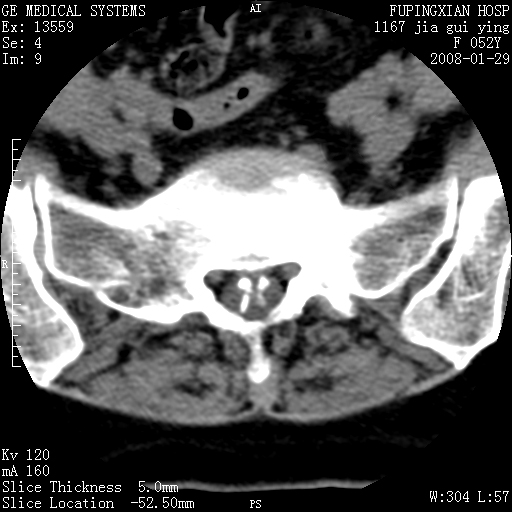

以下是引用zhangzhongshou在2008-1-29 19:34:00的发言:[br]1、腰椎退行性变。[br]2、硬膜囊内钙化,多考虑蛛网膜炎所致粘连钙化

以下是引用dyqct在2008-1-29 21:49:00的发言:[br]考虑:1、腰4-5椎间盘突出(左椎间孔外侧型)。[br] 2、硬膜囊内钙化,多考虑蛛网膜炎所致粘连钙化,请询问病史病人以往做过碘油造影吗?

以下是引用liuyue在2008-1-30 4:32:00的发言:[br]1. 腰4-5椎间盘突出。[br]2. 硬膜囊内钙化,考虑a.蛛网膜炎所致粘连钙化;[br] b.硬膜囊内血管畸形.[br] c脊髓纵裂畸形.[br] 另:询问病史病人以往做过碘油造影吗?